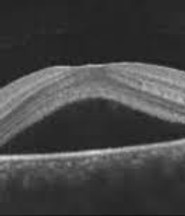

Ms Heng is a medical retina specialist and provides service in diseases of the retina, including consultation and follow up of Age related macular degeneration, prevention advice, Diabetic Retinopathy Screening and treatment, Retina Vein Occlusion treatment and follow up, Central Serous Retinopathy follow up and treatment. She is proficient in cataract surgery and complex retina disease related cataracts and supervises fellows and trainees on her NHS lists. She provides intravitreal injection treatment and lasers for retina diseases and yag capsulotomy.